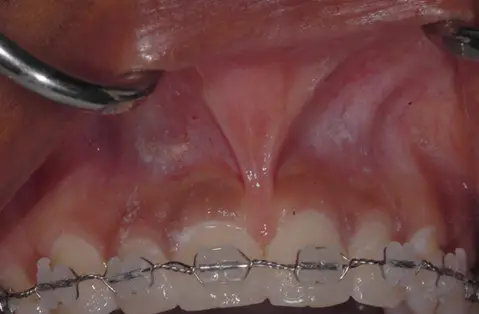

Frenectomy

before

after